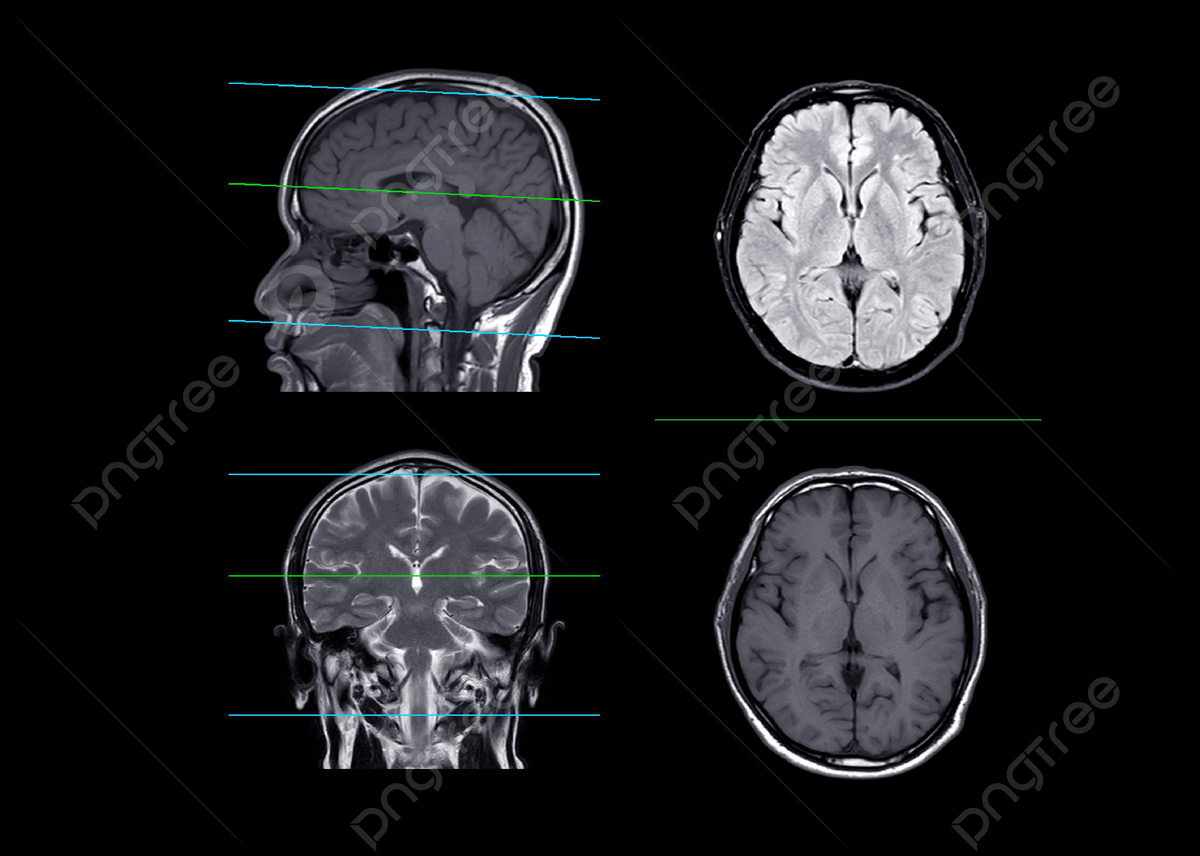

Amazon.co.jp: 脳や鼻腔・口腔などを矢状面と冠状面で観察できる断面模型 - 頭部断面モデル,正中矢状断,前額断 - 3BScientific : 産業・研究開発用品。

大脳 冠状断面<< 神経系 << バイオメディカル CG ライブラリー << 株式会社メタ・コーポレーション・ジャパン。

脳 MRI 3D : 正常解剖学e-Anatomy。

弁護士 小松亀一法律事務所_交通事故_MRI・CT写真の切り口用語解説。